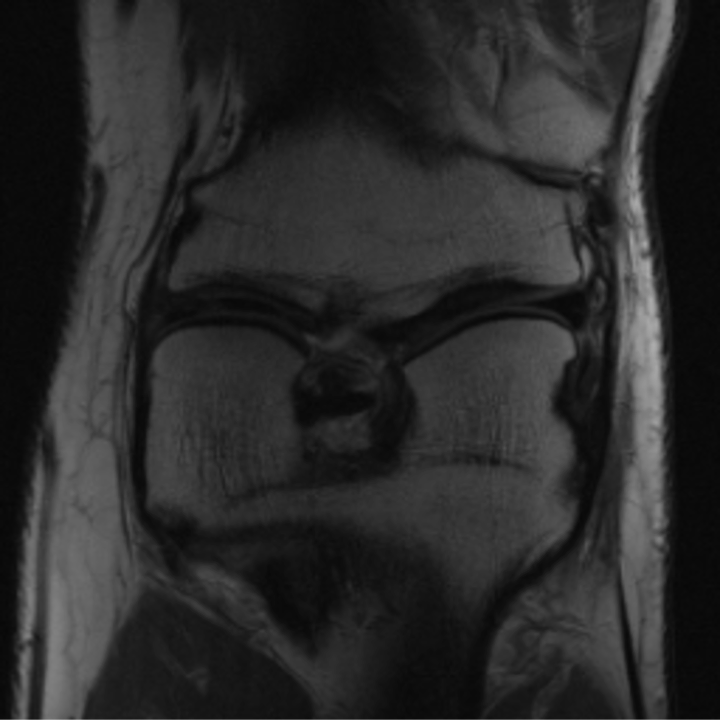

5.3 Out-of-Domain Generalisation

One way to test the generalization capability of the trained X-Diffusion is to test it on a completely different domain from an MRI dataset not seen during training. We report the single-slice results on NYU fastMRI [37, 82], a knee MRI dataset, using the X-Diffusion trained on the BRATS brain MRIs. The results are shown in Figure 9 and Table 2. It shows how successfully X-Diffusion is able to generate knee MRIs from a single image, despite not seeing knees at all in training. To qualitatively assess how realistic our generated 3D volumes were (produced from a single slice), we gave 20 generated examples alongside their real MRI counterparts to an expert orthopaedic surgeon. He was then asked to identify the real example from a given pair. The surgeon identified with certainty only 10 real knee MRIs out of 17, while could not decide on the remaining 3 of the 20 MRI pairs. This further validates the generated out-of-domain MRIs.